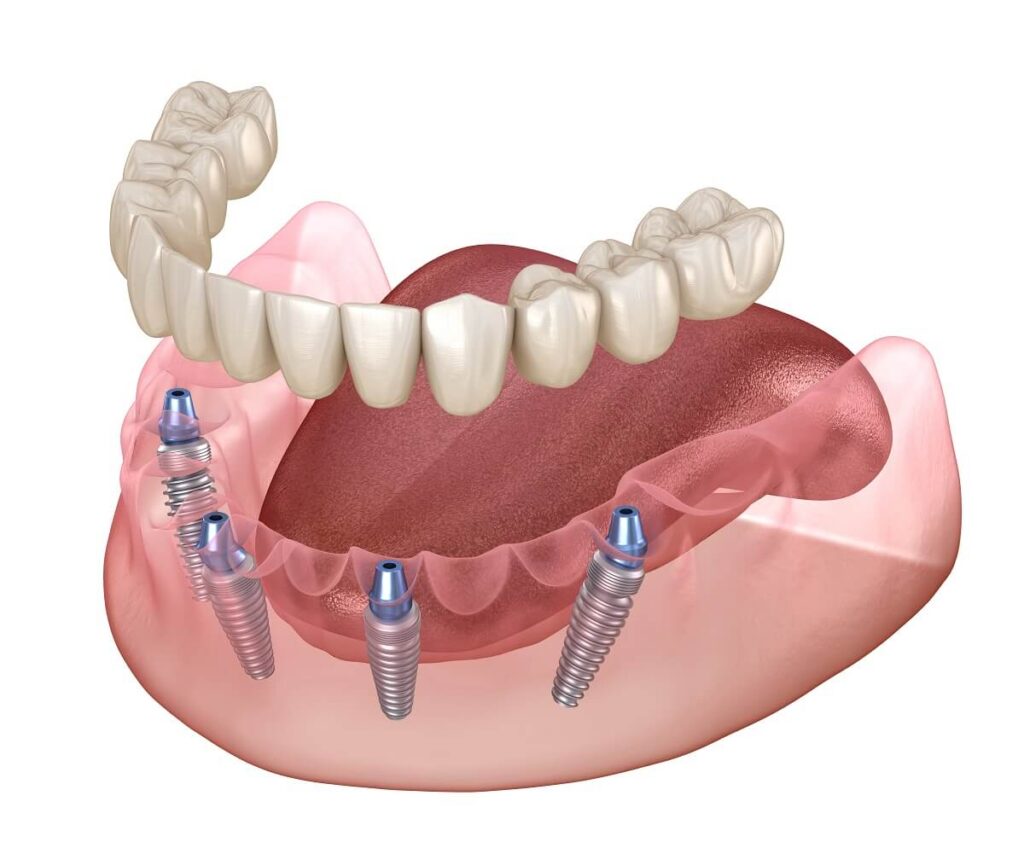

The All-on-4 method is a proven dental implants procedure that provides a full set of teeth to patients using only four titanium implants per jaw. With this modern technique, patients will regain their standard teeth functions and experience a confidence boost with a natural smile at a very affordable price compared to the UK or EU. A growing number of patients are traveling for dental implant Turkey treatments, and the All-on-4 option is one of the most requested currently. Let’s see why this is happening.

What is All-on-4 ?